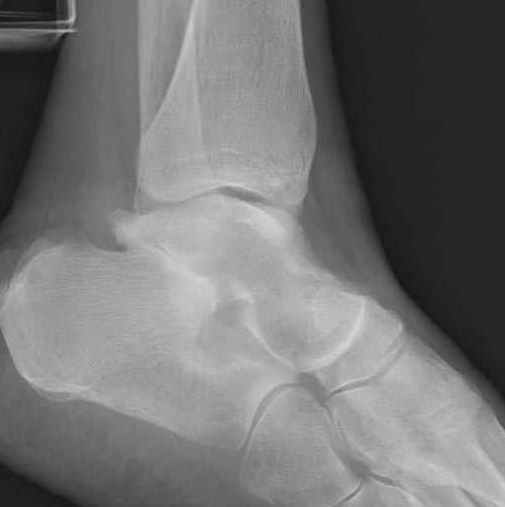

Уважаемые участники русского Ортофорума, поздравляю всех со всеми прошедшими праздниками: Новым годом, Рождеством, Hanukkah, Kwanzaa, желаю участникам всего наилучшего и здоровья.Повреждение таранной кости.Больной 81г автоавария, повреждение таранной кости, здесь снимки. Какие рекомендации?Djoldas Kuldjanov, MDDepartment of Orthopedic SurgerySt. Louis University Medical Center

Вдогонку по поводу перелома таранной кости, больная 81, не страдает диабетом, перелом закрытый, в первый же день поступления ограничились временным наружным фиксатором (как на снимке).

За пару недель насчитал 5 больных с переломом таранной кости, из них двое с двусторонним повреждением.

Из-за отека на стопе тактика лечения у всех была

одинаковая: временная наружная фиксация до спадения отека, при изолированных переломах они выписывались домой и через дней 7 госпитализировались на оперативное лечение.

Примеры на снимке...